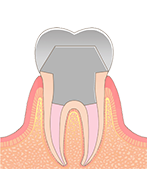

クラウン修復

クラウンとは、インレーでは対応できない面積の広い虫歯や、神経治療をした歯に対して被せる被せ物のことを言います。

歯の神経を取った後に根の長さを測る。

汚染された歯の根の部分を掃除してきれいにします。

根の中に薬を入れて消毒します。

消毒が終わった後に薬などを入れて密封する。

症例によっては金属の土台を入れます。

冠をかぶせます。